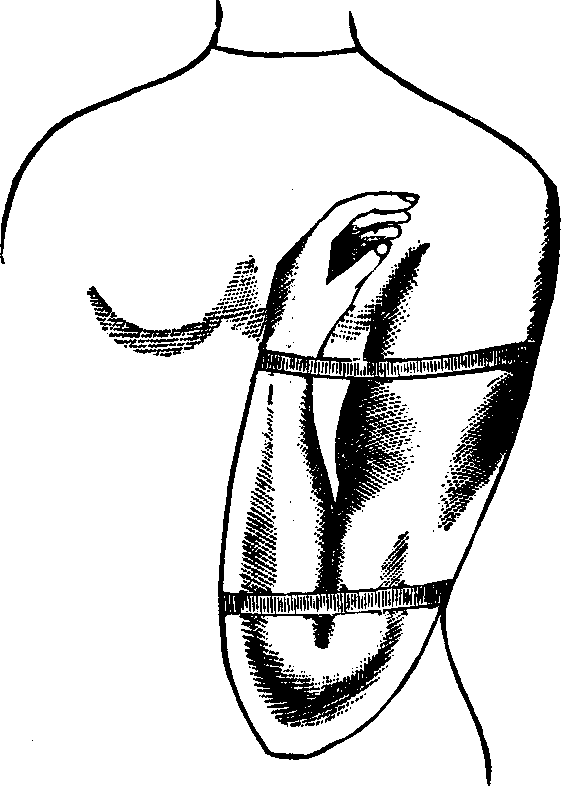

Fig. 4.

WHITE'S HYSTEROTOME. In operating, this instrument is introduced into the

canal of the neck of the womb, when a thumb screw in the end of the handle

is turned, by which a small blade is thrown out from each side, and as the

instrument is withdrawn from the canal an incision is made on each side,

thus enlarging the passage. The upper figure illustrates the instrument

closed, ready for introduction; the lower one, with the blades projected

for cutting.

Many times patients cannot understand why it is that the operation of cutting the constricted cervix causes no pain; they often being entirely unconscious of the making of the incision. The explanation is easy. The cervix uteri, or neck of the womb, is supplied with but few nerves of sensation, and is almost as destitute of sensation as the finger or toe nails, the paring of which causes not the slightest pain. On this account we never find it necessary to administer chloroform or any other anæsthetic when undertaking this operation. If the patient be extremely sensitive the application to the cervix of a weak solution of cocaine is quite sufficient to completely benumb or anesthetize the parts so as to entirely avoid all pain from the operation.